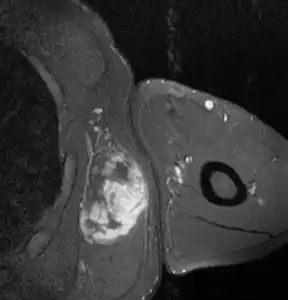

Myxoid liposarcoma

Histopathologic image of myxoid liposarcoma arising in the thigh. H & E stain.

A myxoid liposarcoma is a malignant adipose tissue neoplasm[1] of myxoid appearance histologically.

Myxoid liposarcomas are the second-most common type of liposarcoma, representing 30–40% of all liposarcomas in the limbs, occurring most commonly in the legs, particularly the thigh, followed by the buttocks, retroperitoneum, trunk, ankle, proximal limb girdle, head and neck, and wrist. They occur in the intermuscular fascial planes or deep-seated areas. They present as a large, slow-growing, painless mass.[2]